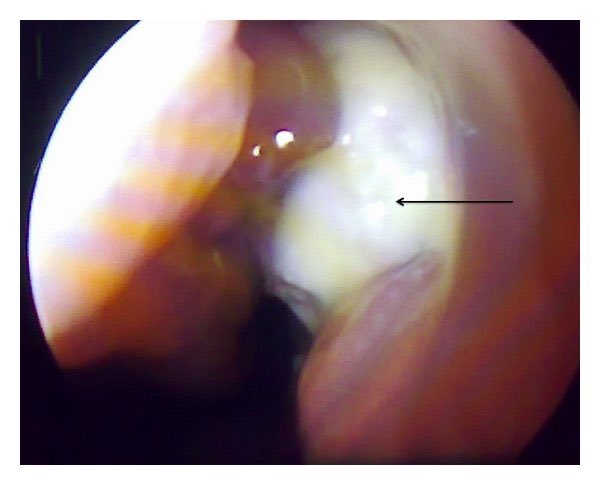

يعرف التهاب الجيوب الانفية المزمن بوجود التالي:

١- انسداد في النفس من الانف

٢- الاحساس بالضغط او الالم او الاحتقان في الوجه

٣- وجود افرازات من الانف سواء من فتحة الانف او بصورة بلغم

٤- نقص او انعدام حاسة الشم